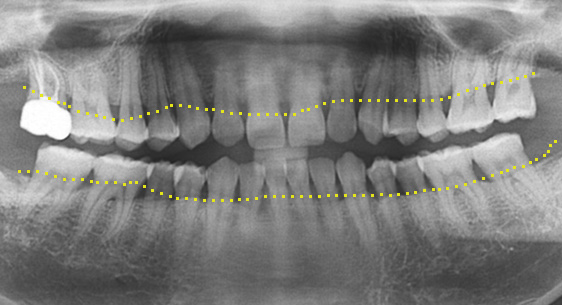

대부분의 치과에선 빼야하는 치아가 있거나 이미 빠졌거나, 신경 치료 후 예후 불량으로 인해 치아를 살릴 수 없는 경우 임플란트를 먼저 고려합니다. 고운미소치과는 인접치아를 움직여 그 공간을 닫아 임플란트 수술이나 보철 치료 없이 자연치를 최대한 활용하는 치료 계획을 세웁니다.

46세 남성환자로 상악동 거상술과 임플란트 진단을 받은 상태로 내원. 치조골이 2/3이상 오염되어살릴 수 없어 발치를 진행, 인접치아를 움직여 발치 된 공간을 닫는 교정치료를 시행하였습니다.